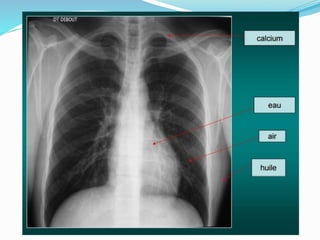

MASSE MEDIASTINALE

 Opacité à limite externe nette convexe vers le poumon

 Raccordement en pence douce

 À limite interne non visible.

 Rappeler des grands signes radioloques (Signe de

silhouette, S.cervico-thoracique, S. convergence hilaire

et S. thoraco-abdominal).

 Rappeller des lignes médiastinales.

 Rappeler des compartiments médiastinaux.